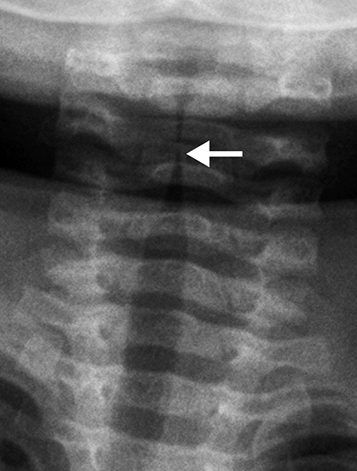

b.png 크루프의 x-ray

x-ray를 찍으면 전형적인 성대 하부의 좁아진 소견이 관찰됩니다.